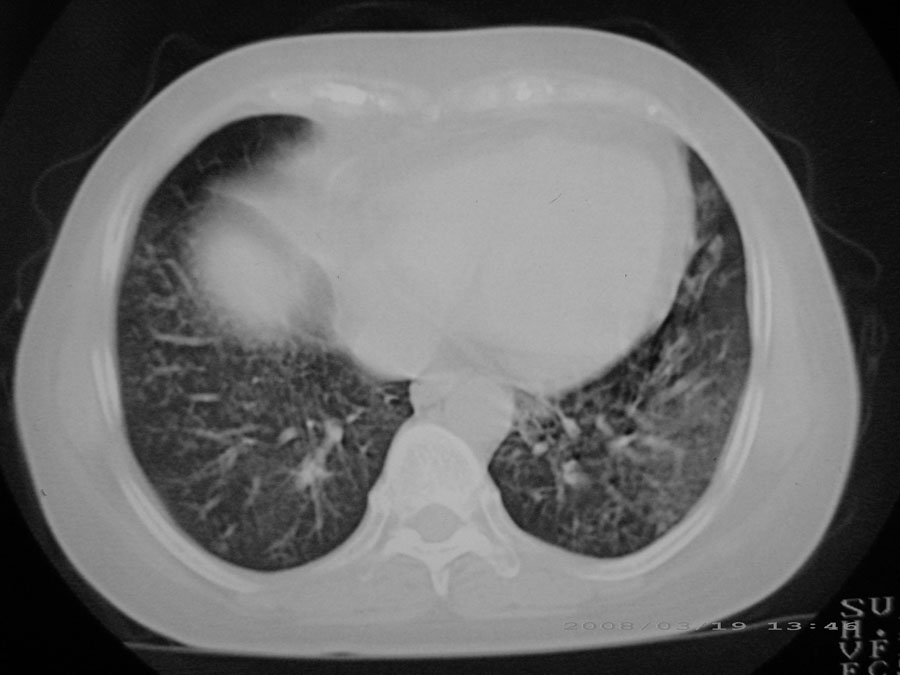

标题: CT13104:胸部大家看看啊,第一次发啊, [打印本页]

标题: CT13104:胸部大家看看啊,第一次发啊,

粟粒性结核

细支气管肺泡癌

本病例主要是癌性淋巴管炎与结节病的鉴别。好好查查吧。

密漫性沿纹理走行小结节影;有间质纤维化;可考虑尘肺;以图而论

血行播散性肺结核

双肺网状结构,小叶间质结节状增厚,考虑结节病

综合大家意见,结核、结节病、肺泡细胞癌均有可能,间质性肺炎暂不考虑,病灶纠集不明显,纵隔未见钙化淋巴结,尘肺可能性不大,但还是要密切结合临床诊断。

今天重新仔细看了看,矽肺确实不能除外,病灶主要表现为间质结节及纤维化。好好问问病史吧。